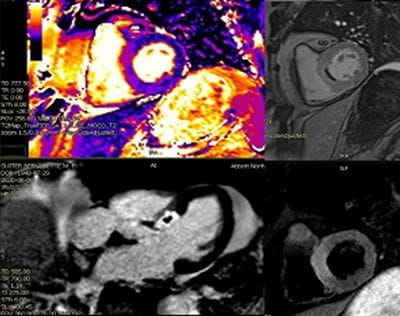

• Dedicated state-of-the art Cardiac MRI and CT imaging program (1.5T Siemens Aera; Dual-Source Siemens Force, Siemens Drive, and Flash scanners) with dedicated CMR techs and CT techs.

• Strong collaboration with NIH-NHLBI with early access to research CMR sequences.

• High volume program with daily case averages of 10 CMR studies and 25-35 cardiac CTAs (50% coronary CTA, 30% structural, 20% other). Broad case complexity, including CAD, structural heart pathologies, congenital heart disease,  and implantable devices. Routine use of cutting edge technology, including T1/ECV mapping, quantitative perfusion, free-breathing CMR exam, artificial intelligence based CT analyses, CT-FFR, structural planning and simulation.